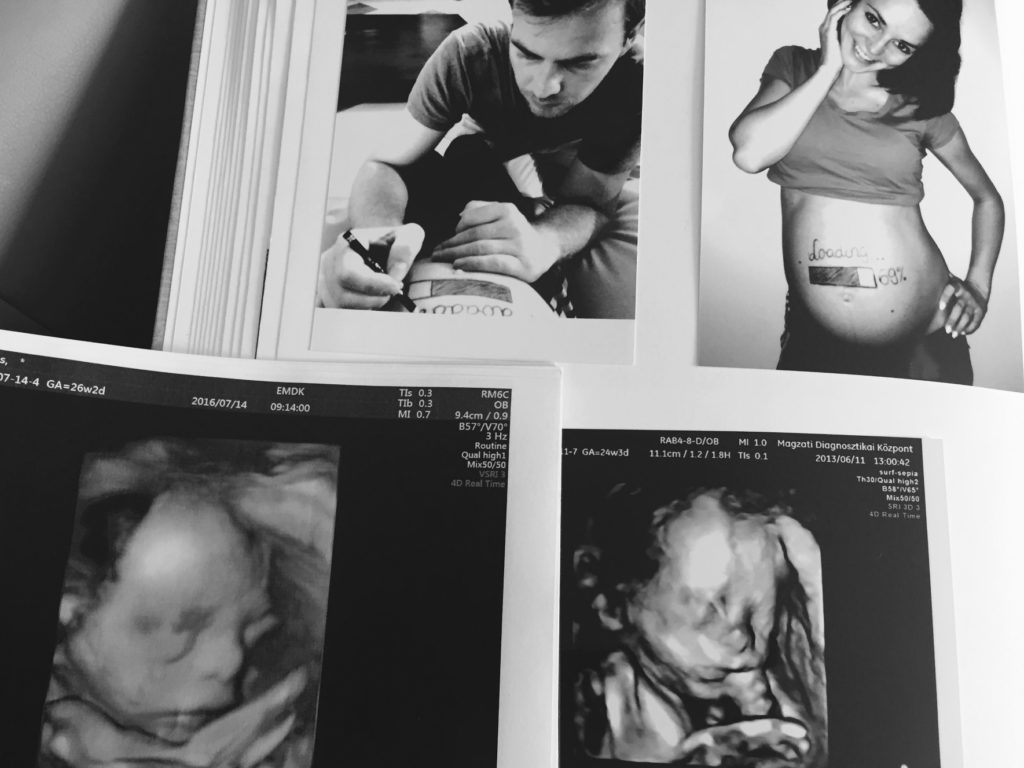

A család legfiatalabb tagja, Benediktnagyon izgatottan várja kistestvére megérkezését. „Beni egyre többször kérdezi meg tőlem, mikor születik már meg az öccse. Örömmel tölt el, hogy azt válaszolhatom neki: már nem kell sokat aludni, hogy ne csak az ultrahang képen, hanem szemtől szemben is láthassa a testvérét – mesélte mosolyogva a csinos kismama, aki már minden fontos vizsgálaton túl van. – ACzeizel Intézetben voltunkbabamozin, és kiderült, hogy az új családtag szakasztott bátyja! Egyből feltűnt, hogy születendő kisfiam pont úgy néz ki, mint Benedikt, amikor a pocakomban volt. Hazaérve azonnal egymás mellé tettem a két ultrahang képet, és az összehasonlítás csak megerősített: a két fiú teljesen egyforma” – tette hozzá kitörő örömmel Dobó Ági.